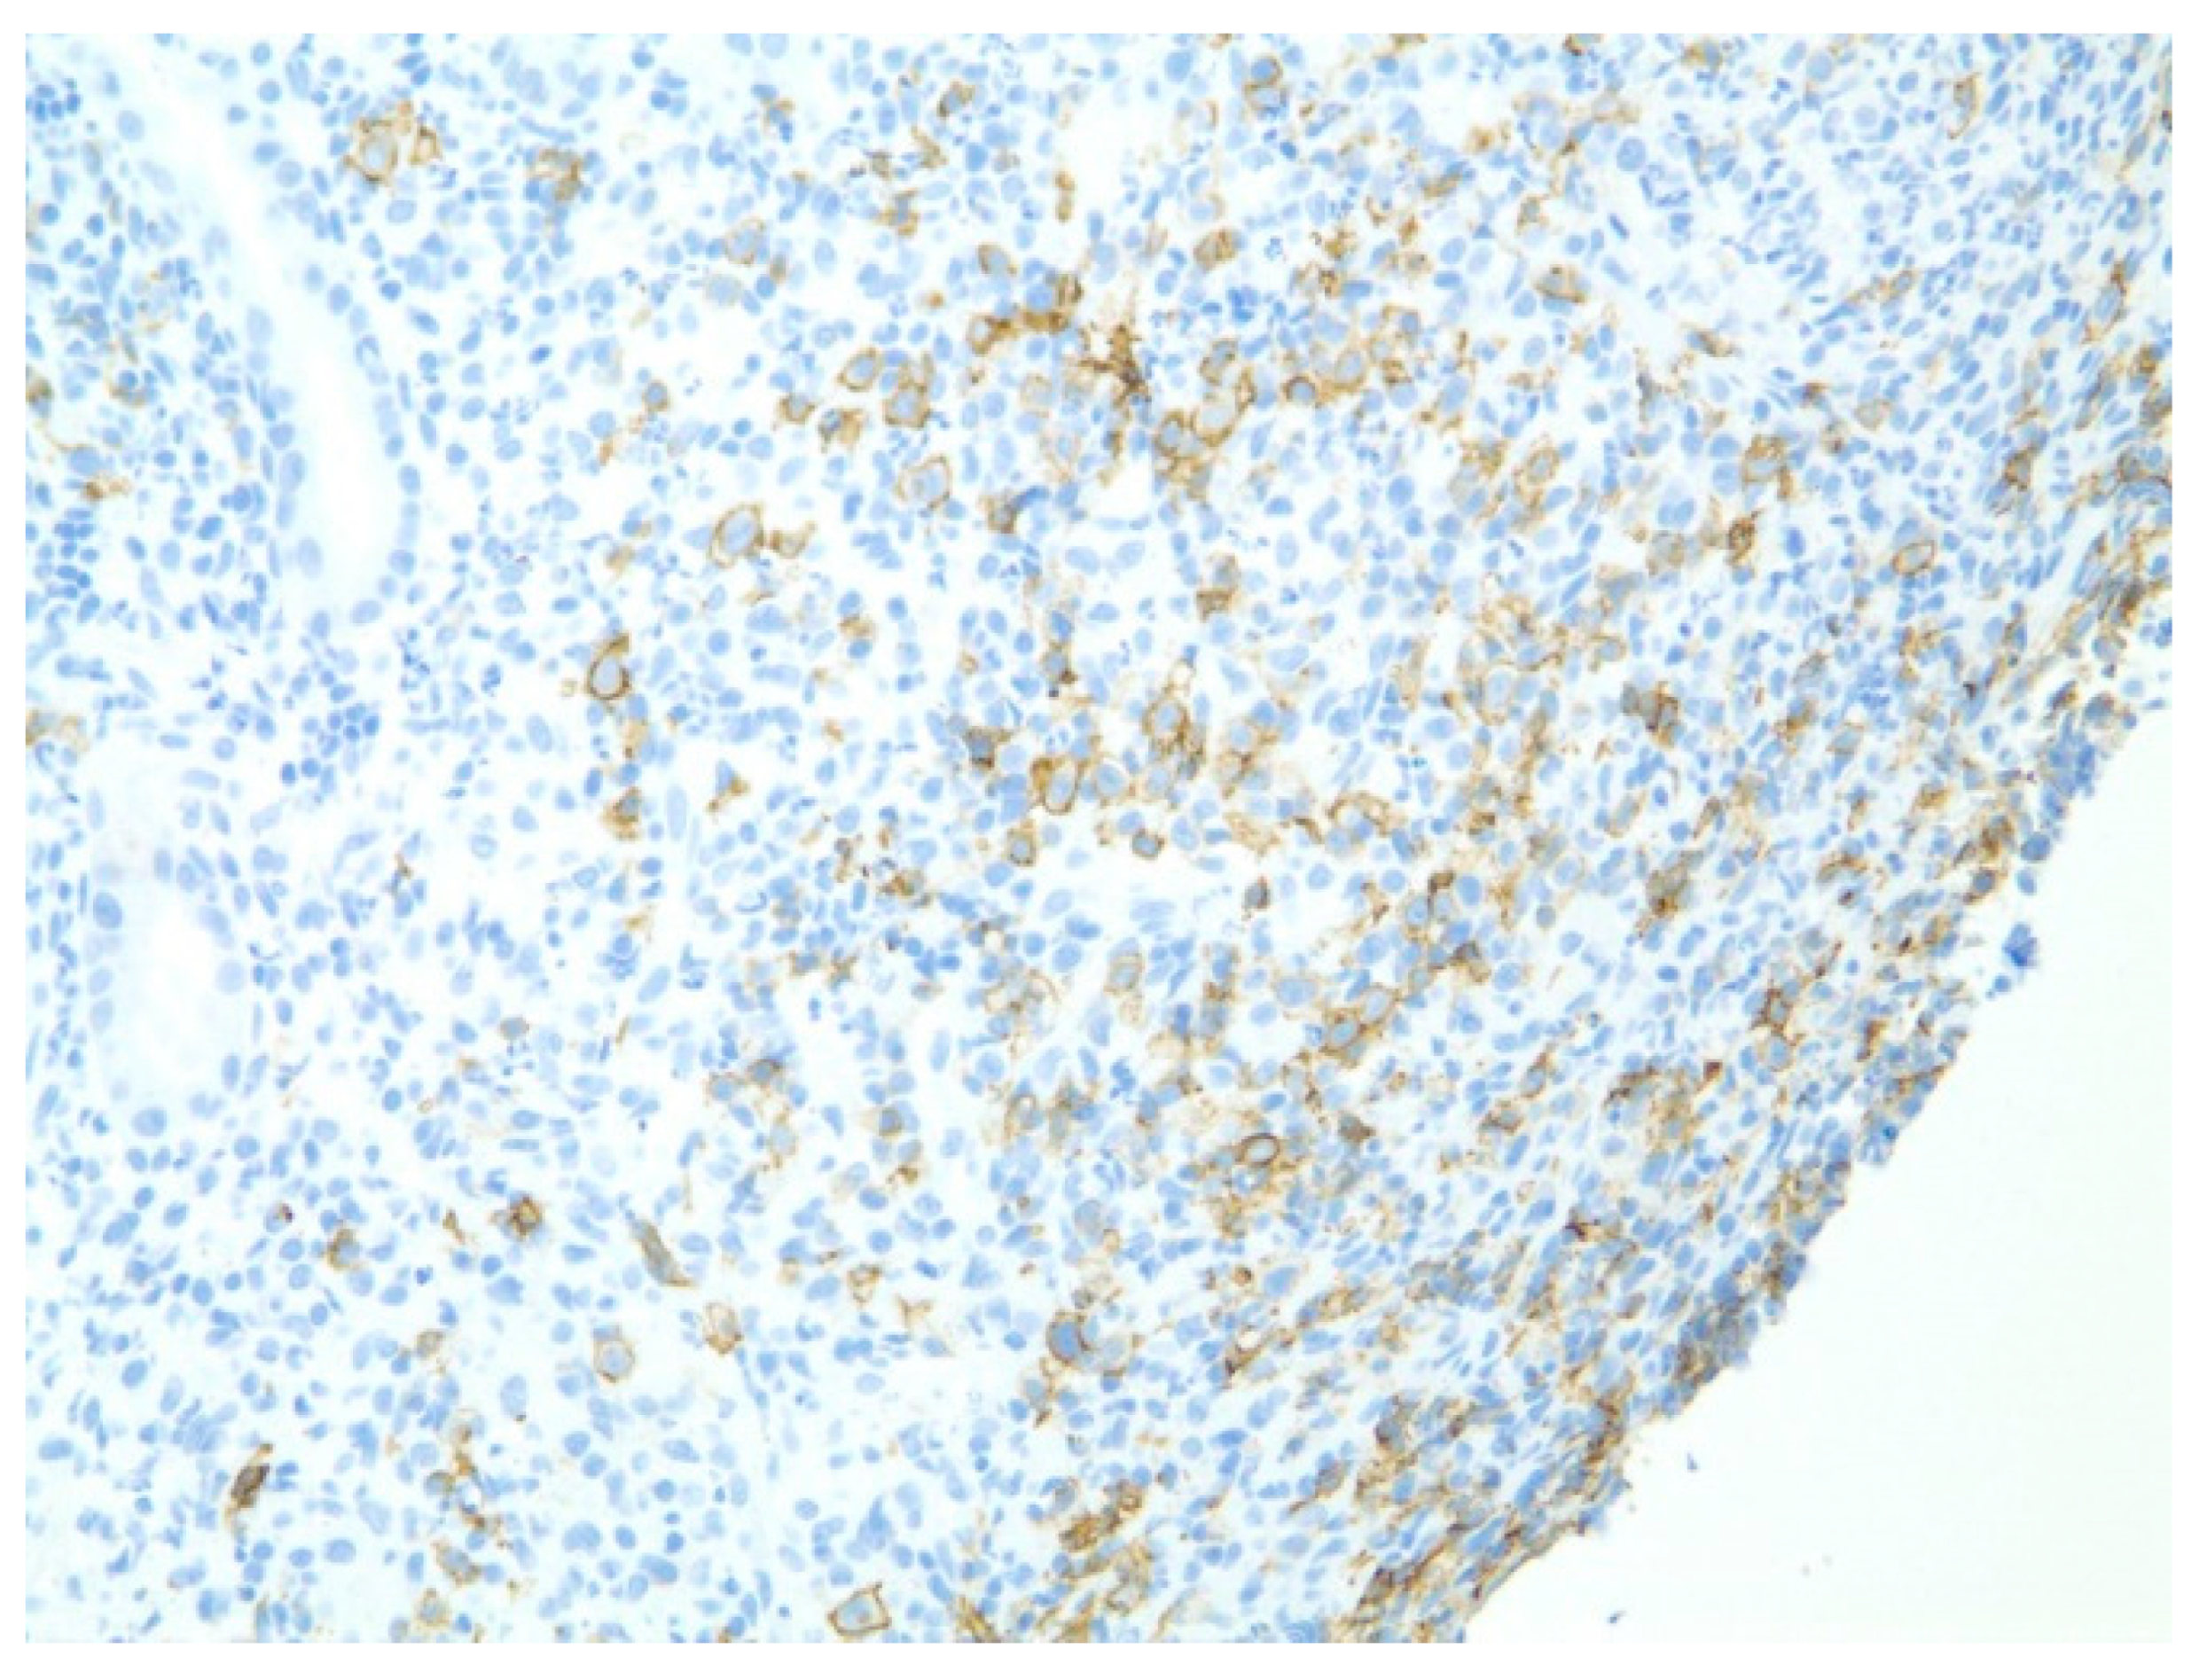

| 1 | F | 66 | Skin | Fundus, cardia, and body | Polypoid lesions with superficial ulcers | Esophagus, duodenum, mediastinum, cervical soft tissue, pancreas | Metastatic malignant melanoma | Radiotherapy and immunotherapy | Comfort care and death 5 days after EGD diagnosis of metastasis |

| 2 | M | 84 | Lymphoid | Fundus and cardia | Ulcerated and necrotic mass | Liver, urinary bladder | Diffuse large B-cell lymphoma | None | Death in 2 months after EGD diagnosis of metastasis |

| 3 | F | 35 | Lung | Fundus | Fungating mass | Esophagus, mediastinum | Large-cell neuroendocrine carcinoma | Chemotherapy-carboplatin/ etoposide | Death 1 month after EGD diagnosis of metastasis |

| 4 | F | 73 | Kidney | Fundus and body | Multiple large friable masses | Liver and lungs | Clear cell renal carcinoma | Nephrectomy, chemotherapy, immunotherapy (Axitinib) | Death 10 days after EGD diagnosis of metastasis |

| 5 | M | 76 | Lung | Body | Cratered ulcers | Liver, bone and adrenals | Small cell carcinoma (poorly differentiated neuroendocrine Ca) | None | Death 7 days after EGD diagnosis of metastasis |

| 6 | M | 61 | Lymphoid | Unknown | Clean based ulcer | None | Marginal zone lymphoma | Rituximab, Zanubrutinib, umbrasilib. OCHOP regimen currently | Progressive disease per latest scans despite therapy |